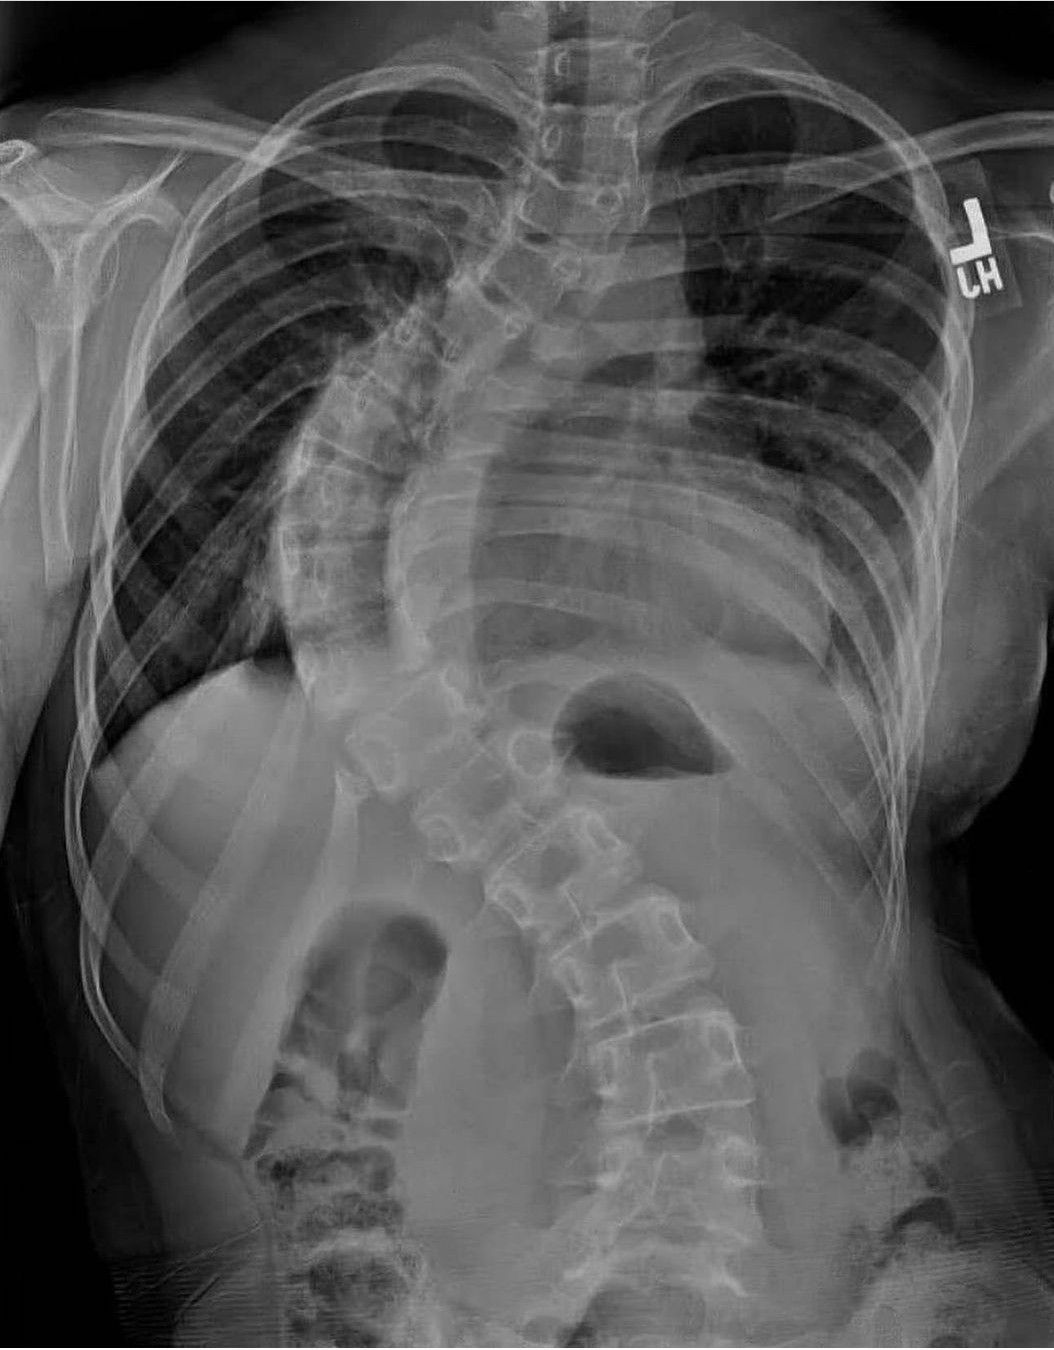

Identify the Pathology

Can you identify the pathology in this radiograph?

Scoliosis